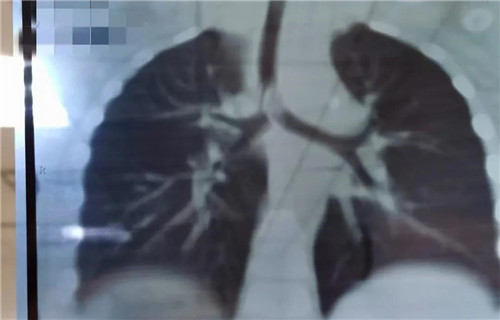

22日晚,19个月女宝诺诺(化名)在家吃花生突然呛咳,爸爸把她倒过来拍几下,诺诺吐出半个花生,但没好转,又出现喘憋,情况非常紧急......夫妻俩立即带孩子来到啪啪网 就诊,耳鼻喉科夜班医生接诊。医生初步判断是气管异物,而且很可能在主气道。肺CT三维重建显示,异物正堵在主支气管与分叉气管交接口,基本堵满了,诺诺出现吸气性呼吸困难。情况紧急,考虑急诊手术取出。当晚9点多,诺诺住院。此时,耳鼻喉科主任沙颖、副主任李莉萍、刚加完班回家的李萍大夫,麻醉科主任王丽波也正在从家往医院赶。

当晚12点,诺诺进入手术室。因为异物占据气道,孩子又小,取异物一定要快。支气管镜进入后显示,半个完整花生堵在主支气管分叉位置,堵塞面积达到4/5以上,仅在花生边缘与气管之间留有少许通气的地方。花生已经被浸泡得很软了,异物钳夹过程中,不能完整夹持,抓出来的都是或大或小的碎块。随着一块一块碎花生被取出,诺诺的呼吸渐渐地好了起来。诺诺被推回病房时,已经快凌晨2点了。